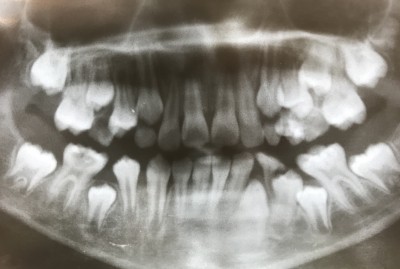

【混合歯列期の床矯正】

2020.03.27 症例紹介